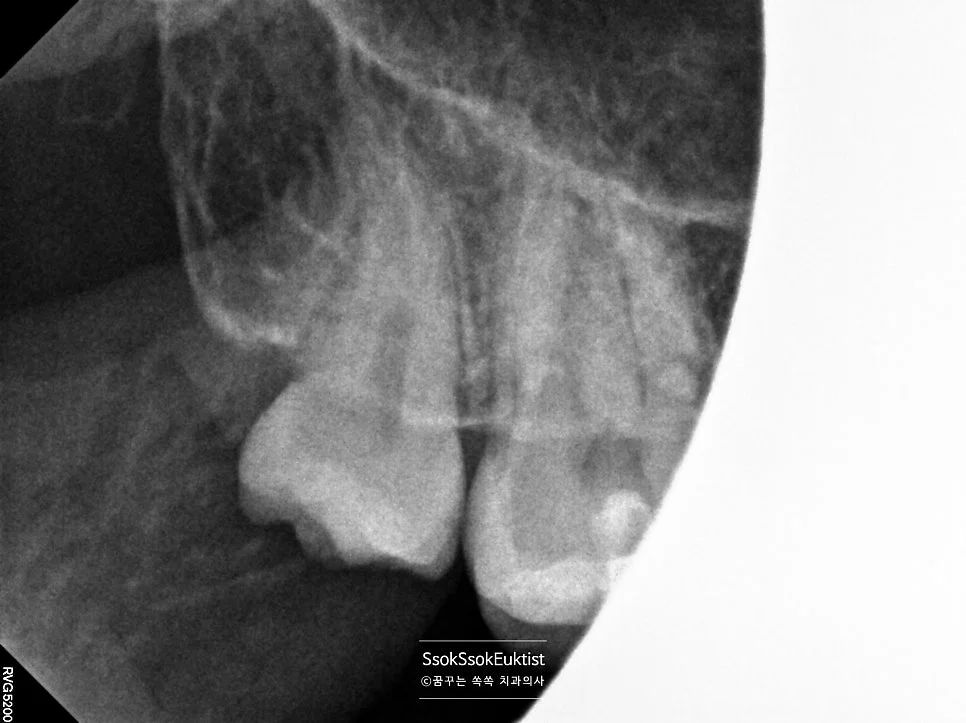

상악 사랑니 방사선 진단

상악 사랑니 — 크기가 작지만 비교적 얌전히 맹출

파란 화살표로 표시되어 있는 치아가 사랑니입니다! 위 사랑니는 크기가 좀 작지만 비교적 얌전히 나있는데요!

아래 두 개의 사랑니를 보면 머리부터 충치가 상당히 진행되어 있는 것을 볼 수 있습니다. 아래 사랑니는 매복 사랑니이기 때문에 발치를 해야 하고, 위 사랑니는 아래 사랑니를 제거하면 닿는 치아가 없어 필요 없고 관리만 안 되는 사랑니이기에 발치를 하는 것을 추천합니다!^^